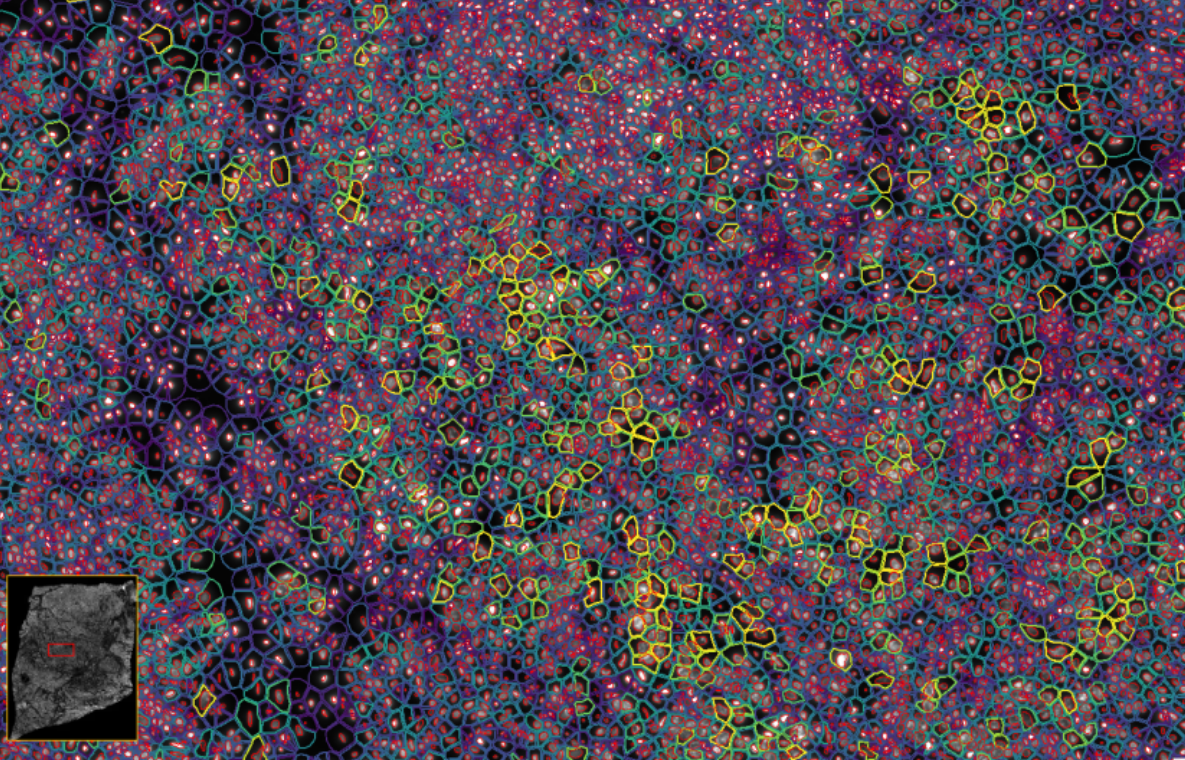

ͼ2£ºXeniumÊý¾Ý¸ÅÀÀ

ͼ3£ºXenium½«¹âÑ§ÌØÕ÷½âÂëΪת¼±¾±í´ï£¬£¬£¬£¬£¬ÊÕÂÞ²¢ÐγÉͼÏñ